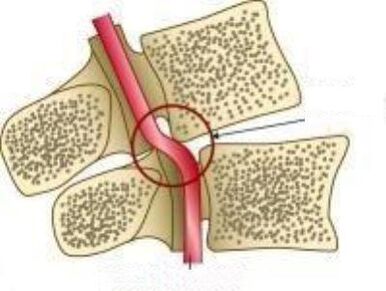

Kung hindi mo pagalingin ang sakit sa paunang yugto, kung gayon maaari itong humantong sa mga komplikasyon tulad ng: protrusion ng intervertebral disc o hernia ng intervertebral disc.

Ang fibrous singsing ay halos nawasak, na humahantong sa mga komplikasyon ng osteochondrosis - protrusion ng intervertebral disc o intervertebral hernia.

- Ang fibrous singsing ng disk ay nagiging mas payat, ang disc mismo ay lumalawak, ay lilitaw na lampas sa mga gilid ng vertebra, pagkatapos kung saan nangyayari ang isang matinding sakit na sindrom.

- Dahil sa pagpapapangit ng fibrous singsing, ang mga nucleus ay nagmumula, na bumubuo ng isang hernia na nakakaantig sa mga kalamnan, arterya, nagbabago ang istraktura ng vertebrae, binabawasan ang sirkulasyon ng dugo ng cerebellum.